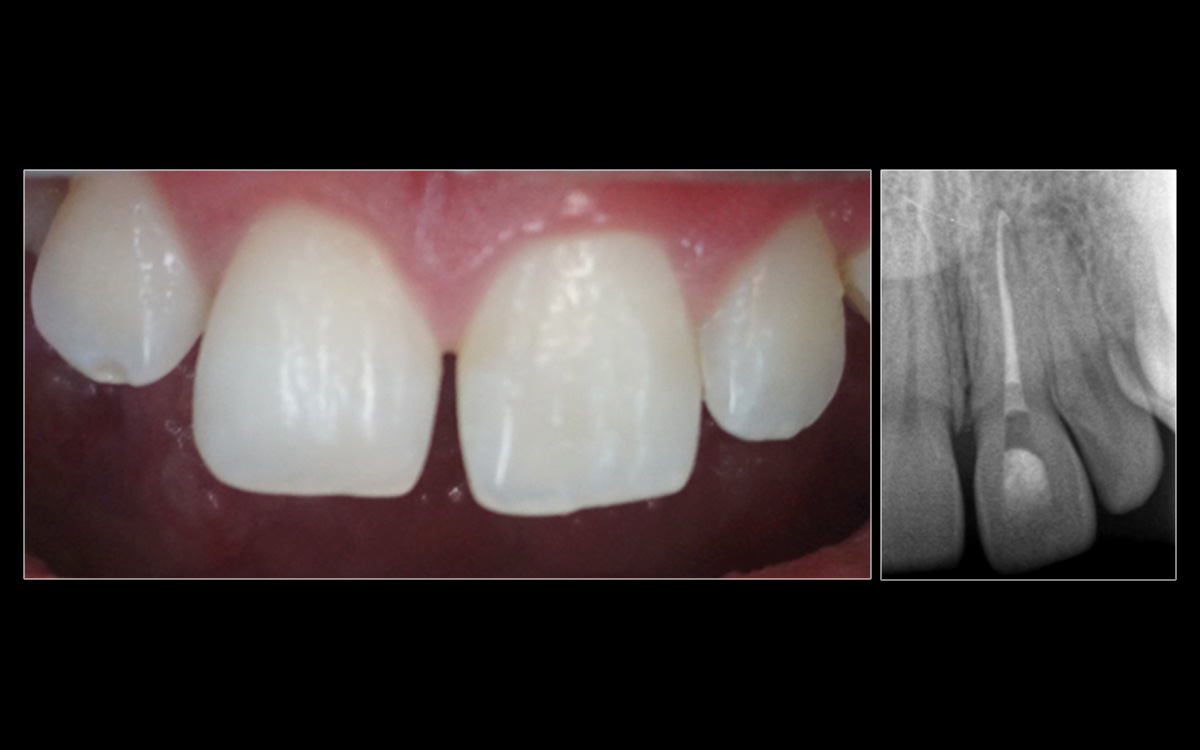

| Patient age | 23 |

| Patient sex | Male |

| Tooth | 21 |

| Chief complaint | My tooth is sore and changing colour |

| Dental history | Patient sustained a knock to the tooth during a brawl over 4 months prior |

| Clinical evaluation | Virgin tooth that is tender to percussion & palpation. No response to sensibility testing |

| Diagnosis | Necrotic pulp and acute apical periodontitis |

| Treatment planned | Orthograde root canal treatment and intracoronal bleaching |

| Treatment | Orthograde root canal treatment over two visits |

| Chemomechanical debridement | Instrumentation with k-file to produce a reproducible glide path, rotary NiTi to finish the preparation & irrigation with NaOCl. MAF X2 (ProTaper Next) |

| Dressing | Ca(OH)2 for 1 week |

| Obturation | With GP & AH Plus sealer. Warm vertical condensation technique. |

| Orifice barrier | GIC |

| Bleach | Sodium perborate for 2 weeks |